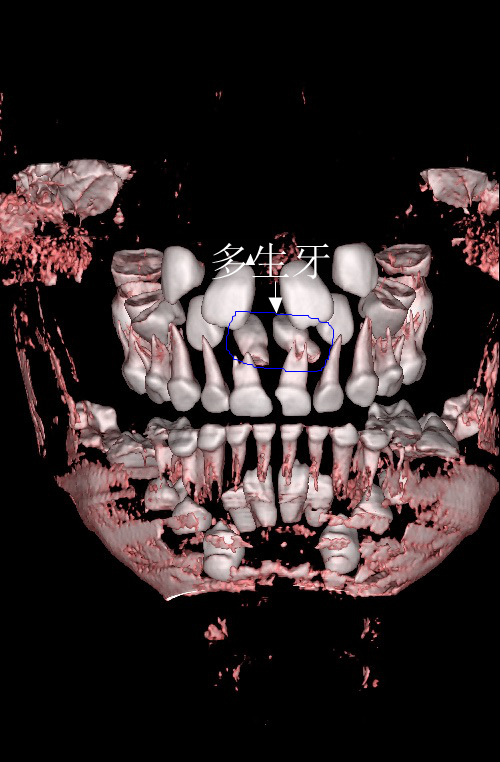

近日,一名门牙疼痛不适患儿就诊我院口腔科,临床检查发现患儿上颌两颗乳中切牙曾于外院充填治疗(补牙),其中一颗急性根尖炎(蛀牙导致牙神经坏死继而根尖发炎)导致了患儿不适。影像学检查发现乳牙根方两颗多生畸形小牙,存在于继替恒牙萌出路径上。口腔科医生首先给予主诉牙开髓引流(消炎),发现患儿极其恐惧口腔治疗,遂与患者家长充分交流沟通决定全麻下治疗两乳牙同时拔除两颗埋植于颌骨内的多生牙。

在麻醉医师精准的麻醉配合下,两颗乳牙的治疗及两颗多生牙的拔除快速高效的完成。这一切均发生在患儿“熟睡”的情况下。术毕,停药,患儿复苏,观察,回家。两颗发炎的乳牙已完成治疗并焕然一新,两颗“恼人”的多生牙已告别小主人。